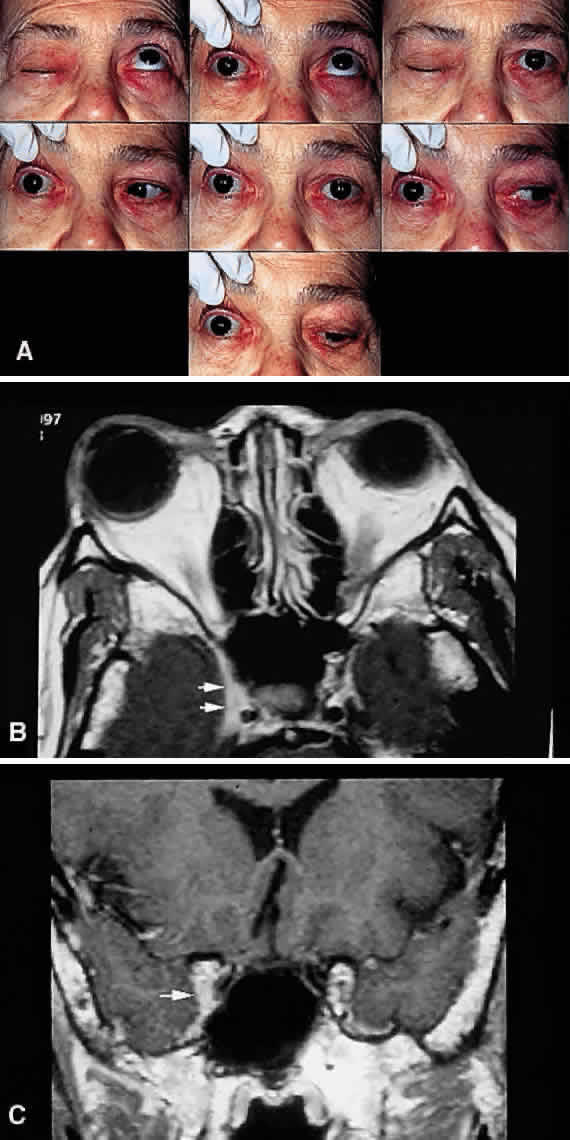

In general, cranio-orbital syndromes may be described as superior orbital fissure syndrome, orbital apex syndrome, and cavernous sinus syndrome (Fig. 15).7,8 The distinction between these presentations depends on the involvement of CN V-2, the sympathetic nerves, and the optic nerve (Table 8). It is much easier simply to call the constellation of signs of cranio-orbital disease the parasellar or sphenocavernous syndrome, rather than attempting to be too specific in an area where the clinical presentations are seldom as distinct as described in Table 8.

Fig. 15. Parasellar syndrome. A. Composite photograph of an elderly patient with periorbital pain in the distribution of the right supraorbital nerve along with complete ptosis and absent levator function (upper left and upper right). When the eyelid was lifted, she complained of diplopia (center). Note the complete external ophthalmoplegia (remaining panels). MRI revealed a mass eroding the anterior clinoid process and extending into the CS and surrounding brain parenchyma. Given the bony erosion, a diagnosis of Tolosa-Hunt would be inappropriate in this case. A transorbital craniotomy for biopsy revealed metastatic adenocarcinoma. A systemic workup failed to reveal a primary site of involvement. The patient' orbital signs responded to radiation therapy. B and C. Axial and coronal MRI of a different patient who presented in an identical fashion. Note the enlargement of the right CS (arrows). Systemic workup was negative, and the patient responded rapidly to intravenous corticosteroids. The lesion disappeared on subsequent scans with no evidence of recurrence after 2 years. A diagnosis of “presumed Tolosa-Hunt syndrome”is acceptable in this case.